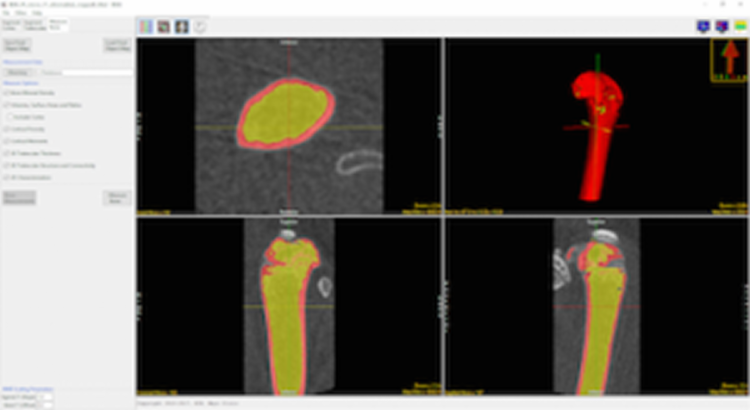

Calculate Bone Measurements

Measurements are automatically calculated for the trabecular and cortical bone and output in several comma-separated value (.csv) files. A utility is also provided to convert CT numbers (HUs) to Bone Mineral Density (BMD) in units of mg/CC.